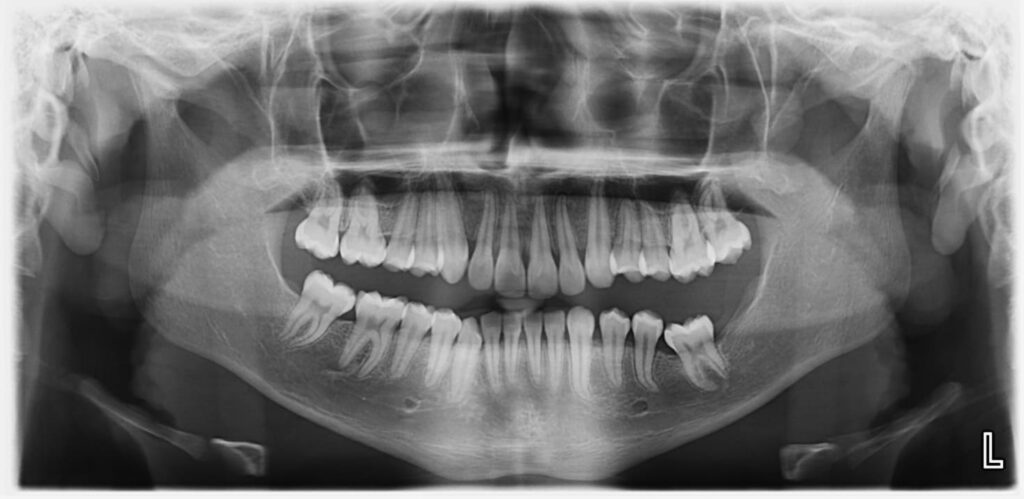

Contamos con equipos PLANMECA PROMAX que permiten realizar estudios panorámicos de formato digital con excelente calidad de imagen.

• Radiografía panorámica digital